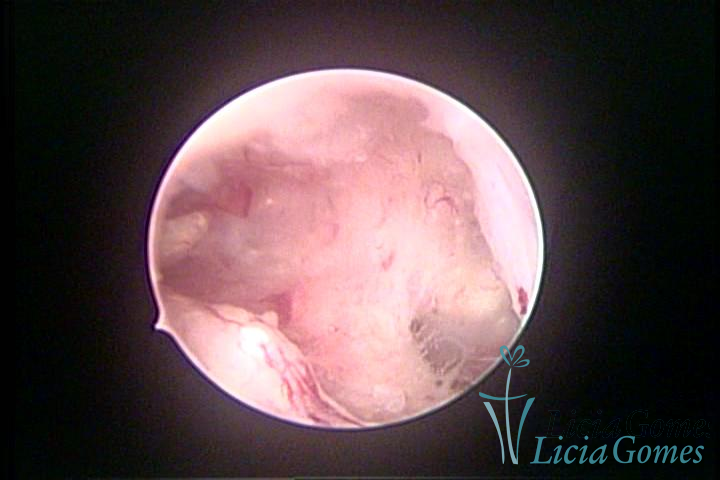

A histeroscopia permite analisar as características da superfície endometrial, não podendo avaliar a profundidade ou o grau de invasão miometrial.

Mas poderá verificar se as lesões são do tipo: focal; regional ou difusa

Este pode apresentar uma gama variável de aspectos macroscópicos, com aspecto pseudopolipoide; lembrando tecido cerebroide ou com reação deciduoide;a vascularização superficial é mais evidente e com vasos em formatos de saca-rolha ou espirais visualizando também a vascularização com atípias, com aumento do calibre dos vasos superficiais, pode ser encontrado também tecido em necrose, poderá haver um pequenos dendritos (papilomatoso).